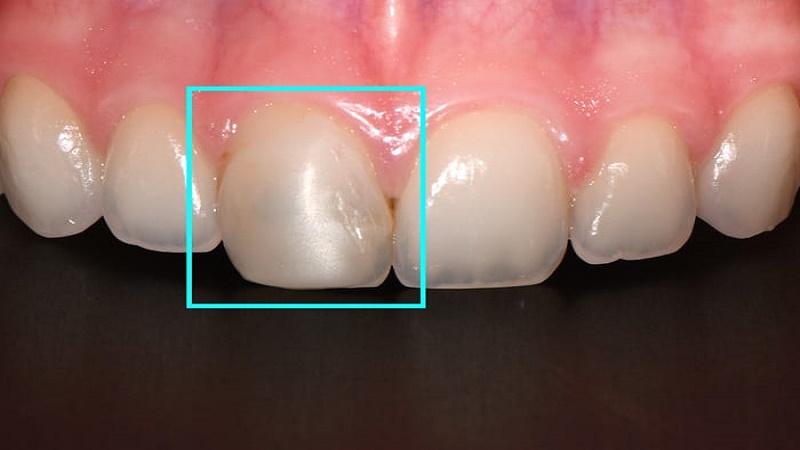

- ترمیم های همرنگ دندان در اصفهان